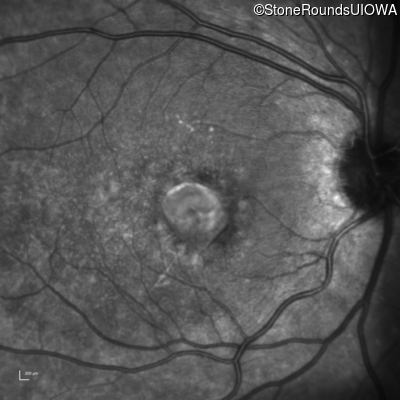

Infrared Fundus Photograph - Right - 20/100 +1 sc

Exemplar